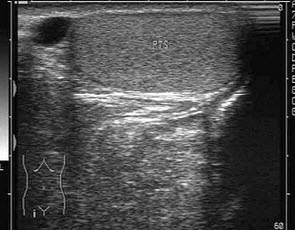

14、单项选择题

如图,最可能的诊断是()

A.软骨成长不全

B.致死性骨发育不全

C.窒息性胸廓发育不良

D.肢体屈曲综合征

E.无肢畸形

15、问答题 SAM征是指什么?